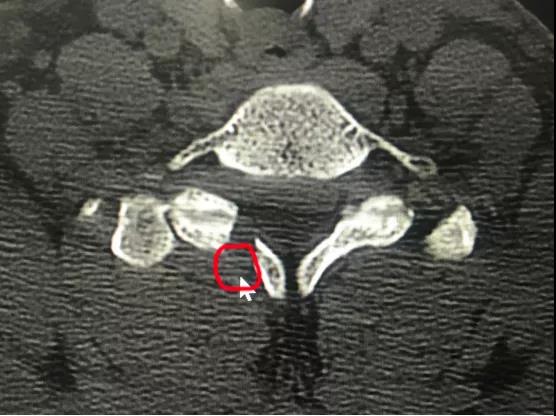

颈椎前路间盘摘除椎管减压植骨融合内固定(ACDF)是经典的手术方式,但要牺牲一个颈椎运动节段。近日,*安泰**市中心医院脊柱外科收治宁阳患者张某,45岁,颈部不适2月,右上肢疼痛麻木1月余。采用牵引、药物等治疗,效果欠佳。疼痛无法缓解,严重影响睡眠。入院诊断颈椎间盘突出症,完善X线、CT、MR相关检查显示:颈6/7椎间盘突出,向下方脱垂至颈7椎体中下方,压迫脊髓。由于颈椎椎间盘突出高度脱垂,至椎间隙下方较远,采用传统ACDF,从前方椎间隙根本无法取出脱垂的间盘组织。科室采用局部麻醉,颈椎后路“钥匙孔”技术,通过在颈7右侧椎板用高速磨钻磨出一个7毫米的小孔,直达病变部位,将高度脱垂的间盘顺利取出,患者术后疼痛即刻消失,由于局部麻醉,增加了手术的安全性,患者术后就能够正常下床活动,手术第2天出院,受到了患者及家属的好评。

神经根型颈椎病是最常见的颈椎病类型,由于颈椎神经根活动度较小,“黄豆”大小的的颈椎间盘突出就可以引起剧烈疼痛,脊柱外科开展脊柱内镜治疗颈椎间盘突出技术(“钥匙孔”技术)已经有3年时间,具有“三好一满意”(1、外观好,颈部后方只有7毫米切口,一般愈合以后看不到切口;2、内镜下视野好,放大约4-10倍,清晰,完全不破坏脊柱稳定性,不需内固定,微创,安全;3、疗效好,通过透视定位,直达患处,直接解除神经压迫;4、患者满意,术后即刻解除症状,早期下地,早期恢复工作生活。)的优势。脊柱外科通过此技术已治愈近100例患者,都收到取得良好的治疗效果。该患者高度脱垂型的颈椎间盘突出采用内镜下颈椎后方椎板“钥匙孔”技术,是在掌握熟练的颈椎内镜技术的情况开展的,此手术的成功开展,标志着*安泰**市中心医院脊柱外科颈椎内镜技术又跨上一个新的台阶。